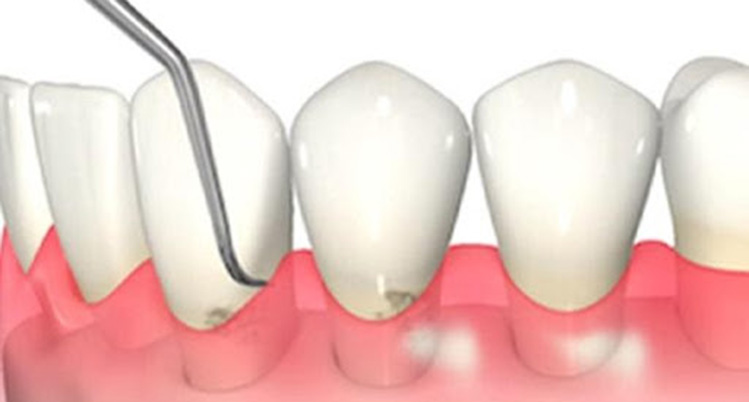

3. SRP

(スケーリング・ルートプレーニング)

専用の器具を使って、歯ぐきの中にある汚れを除去して、歯の根っこ部分の表面を汚れの付着が起こりにくい状態に仕上げる処置です。

主に、歯ぐきの中にまで歯石が入り込んでいる中等度以上の患者さまに対して行います。痛みが強い場合は、麻酔をして行うこともあります。

歯と歯茎の間の汚れをかき出すイメージイラスト